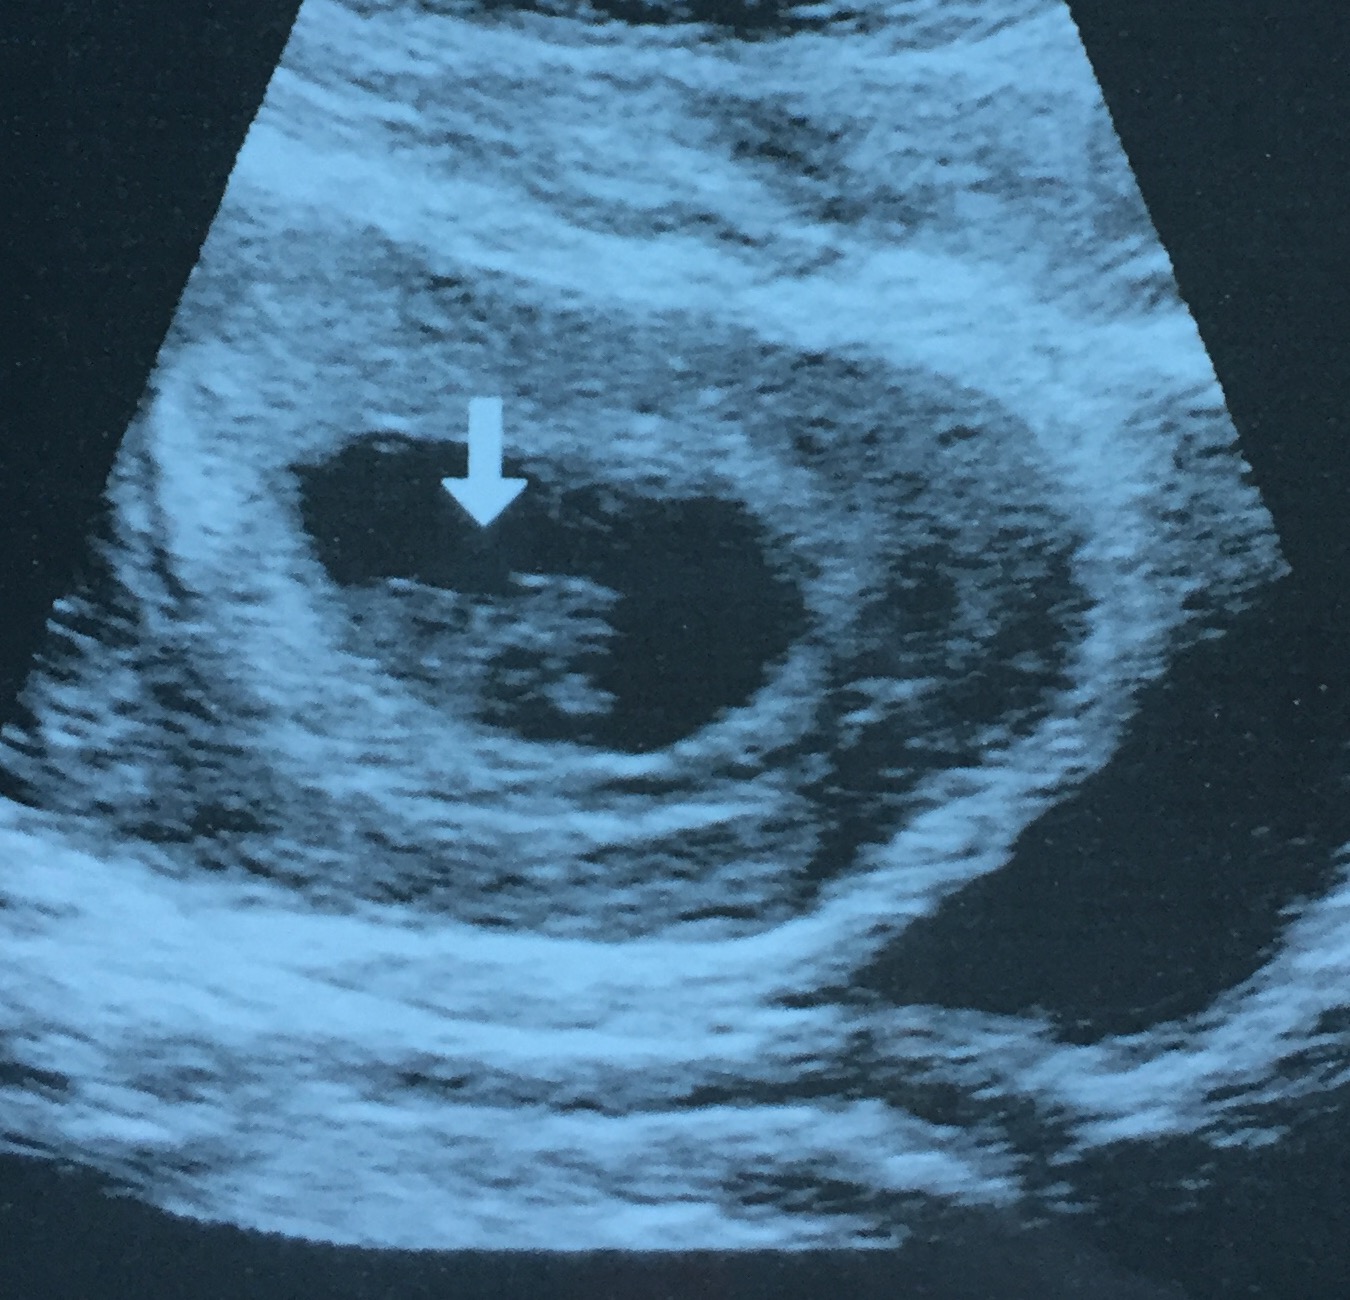

• I guess I can get in on the fun here! My ultrasound isn't very exciting - I thought I was over 8 weeks when I went in but US showed me at 6 weeks. This was almost three weeks ago now but I probably won't get another look until 19 weeks!